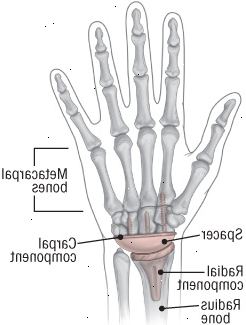

Poškození zápěstí spoj je nahrazen umělým kloubem, který obsahuje několik kovových složek. Radiální složka vloží do poloměru kosti, a karpálního složka je zajištěna do karpálního kosti. Polyethylen Distanční plochou na jedné straně a kola na straně druhé, se hodí do složky karpálního a skály na radiální složky. |

Zápěstí kloubu může být provedeno v celkové anestezii nebo regionální blokové anestezie jako ústavní nebo ambulantní zákrok. Chirurg odstraní první řádek zápěstních a záprstních kůstek a tvary konec poloměru (hlavní předloktí kostí), aby se vešel na protézu. Radiální složka kloubu je vložen do poloměru předloktí, přičemž karpální složka je vložen do ruky kosti. Polyethylen (high-kvalitní plast) spacer zapadá mezi dvě složky (viz obrázek).